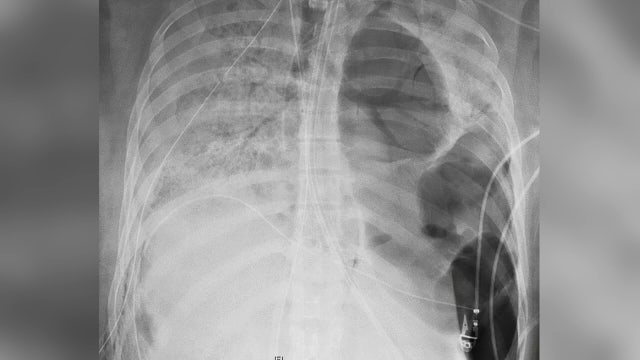

COVID-19 damages lungs of asymptomatic and most severe patients alike, scientists believe